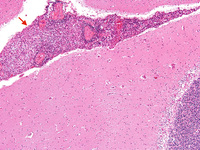

Biópsia do cérebro de paciente imunocomprometido com meningite criptocócica sob baixa magnificação. As meninges estão expandidas (seta), mas o córtex está relativamente não envolvido histologicamente

Do acervo pessoal de Robert E. Schmidt; usado com permissão